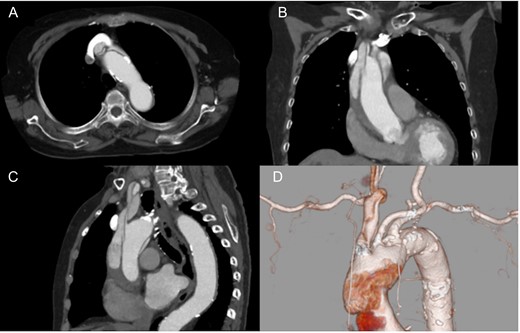

An 86-year-old woman with acute type A aortic dissection was transferred to our institution. Contrast enhanced computed tomography (CT) showed aortic dissection involving the ascending aorta extending to the proximal descending aorta. The true lumen of the brachiocephalic artery was occluded by the false lumen (Fig. 1). No neurological symptoms were present preoperatively. The patient was transferred to the operating room, and underwent central aortic repair with ascending aortic and bicaval cannulations. Cerebral perfusion was monitored with near-infrared spectroscopy (INVOS cerebral oximeter, Somanetics Inc, Troy, USA) and transcutaneous carotid echo. Inside the aorta, the orifice of the brachiocephalic artery was completely occluded by the false lumen. Selective cerebral perfusion (SCP) through the brachiocephalic artery was initiated immediately, however, the SCP flow was not sufficient due to stenotic lesion with low right side regional oxygen saturation (rSO2). Considering low rSO2, it was felt that the lesion should be treated even without preoperative neurological symptoms. The S.M.A.R.T. Vascular Stent System (Cordis Corp, Fremont, CA, USA) (12 mm × 40 mm) was inserted and deployed inside the brachiocephalic artery. After SCP cannula was inserted through the stent, right side rSO2 increased similar to the left side. Finally, ascending aortic replacement by using 26 mm J-Graft (Japan Lifeline Co., Ltd., Tokyo, Japan) was performed. Postoperative course was uneventful without any neurological event. Postoperative CT scan showed good stent patency and no residual dissection in the brachiocephalic artery (Fig. 2).

Postoperative computed tomography showing patent carotid stent and no residual dissection. Axial (A), coronal (B) and sagittal view (C). 3D computed tomography angiography (D).